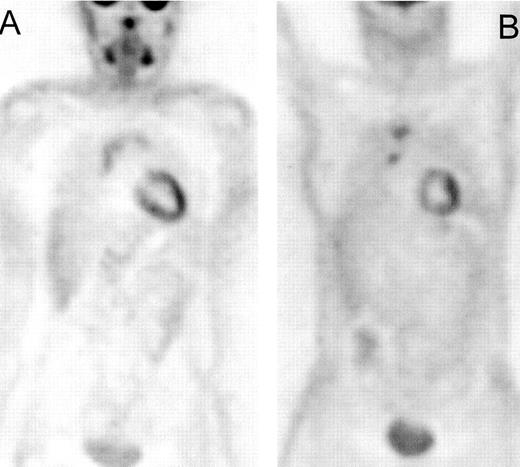

Patient with Hodgkin’s lympoma, nodular sclerosis, stage IIB based on conventional imaging modalities (computed tomography [CT] and iliac crest biopsy).

Positron emission tomography (PET) also showed increased fluorodeoxyglucose (FDG) uptake in the lumbar spine suspected for bone involvement (A) upgrading this patient to stage IVB. PET after 4 cycles of ABVD (Adriamycin®, bleomycin, vinblastine, dacarbazine), (B) only showed increased FDG uptake in bone marrow secondary to marrow regeneration. The hot spot in the spine has become cold representing replacement of the bone marrow by nonviable tumor tissue.

Compared with gallium scintigraphy, FDG-PET appears to have advantages that include inherent superior resolution, higher sensitivity (especially in the abdomen and bone), lower radiation burden (10 mSv/PET versus 44 mSv/gallium scintigraphy) and a shorter examination time (2 hours for PET versus 3 days for gallium scintigraphy).3,4 FDG-PET was also found to be more sensitive and specific than bone scintigraphy for the detection of cortical bone involvement5 and complementary to bone marrow biopsy for detection of marrow involvement distant from the biopsy site (Figure 4 ).6